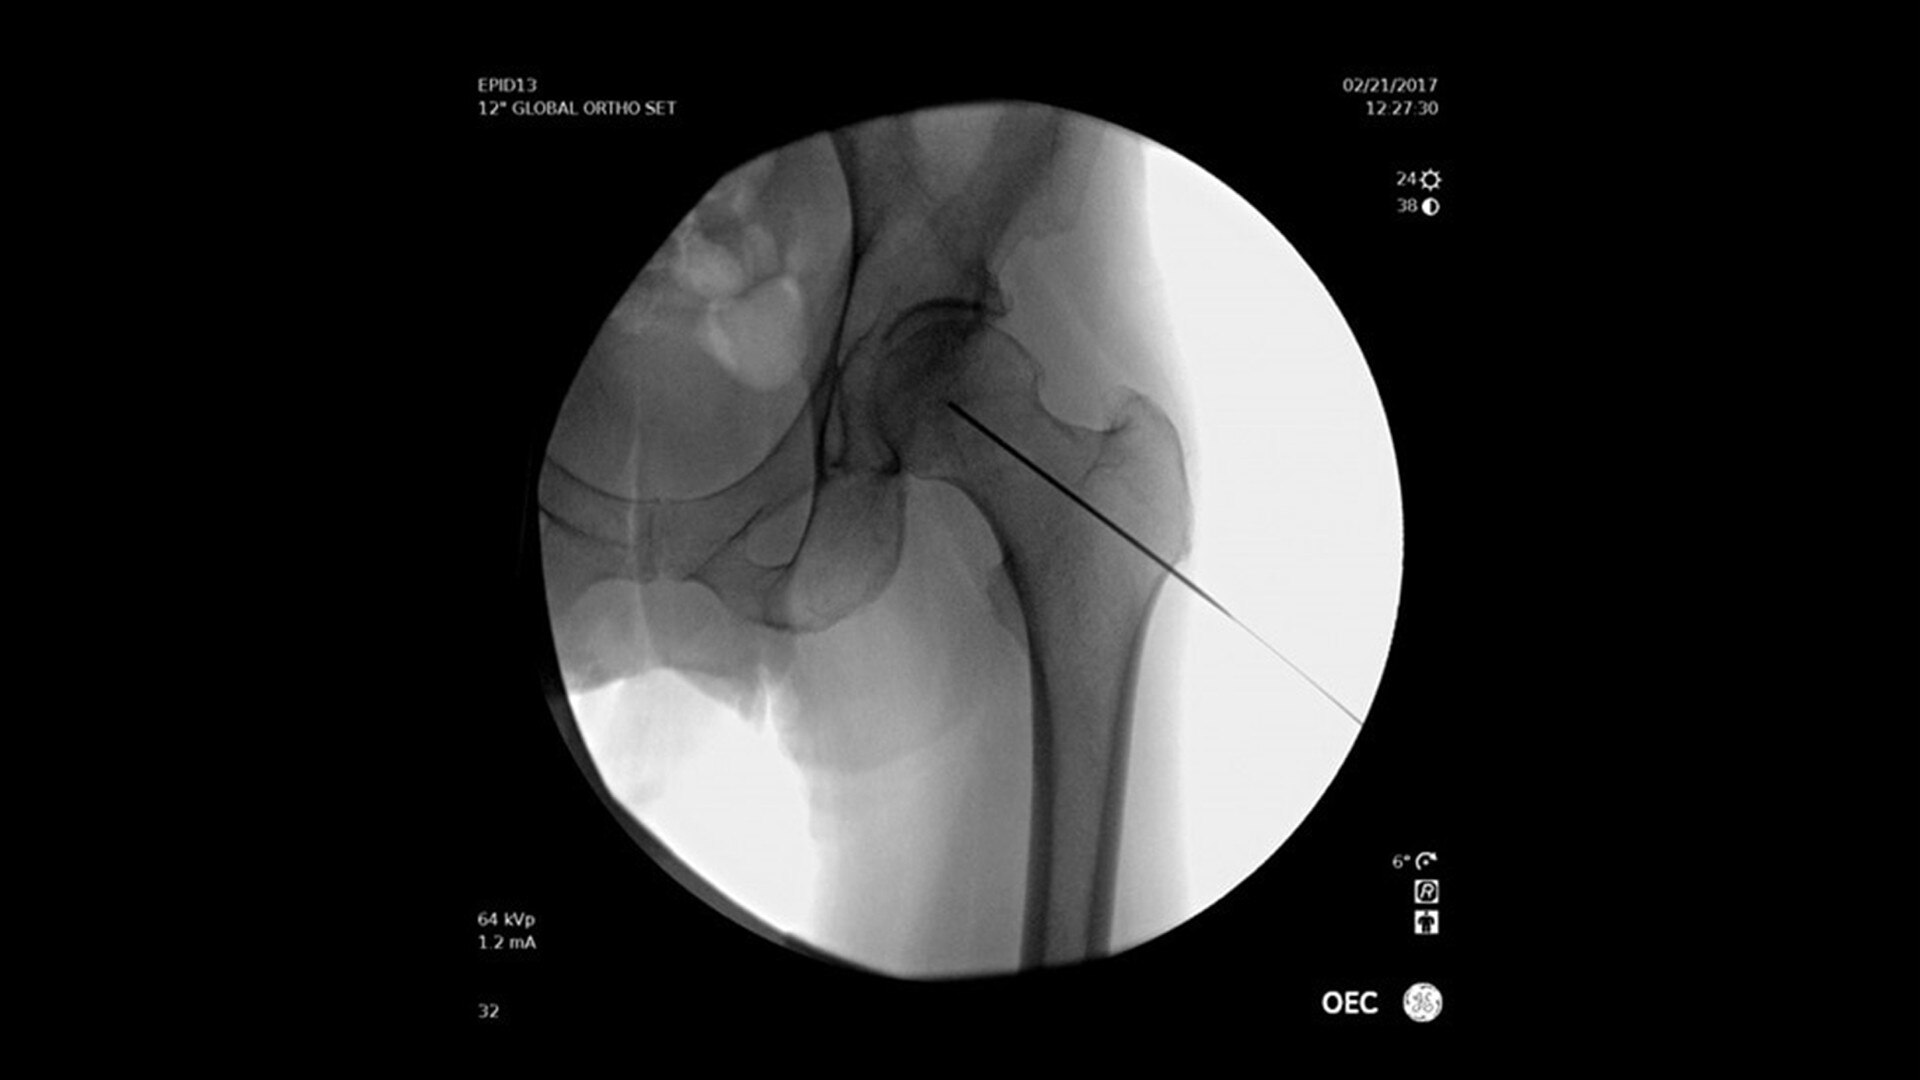

View the anatomy in detail

The system features 3D CT HD³, GE HealthCare's next generation of 3D imaging, providing fine image details for visualizing soft tissues and small devices such as intracranial stent struts.

Superb image quality with high Detective Quantum Efficiency (DQE)

The proprietary angiography flat-panel detector offers one of the industry’s highest ratings for Detective Quantum Efficiency (DQE), a parameter internationally acknowledged as an index of detector performance in contrast-and dose-limited imaging performed in clinical studies. High DQE enables better-quality images at the same dose, or the same quality image at a lower dose.